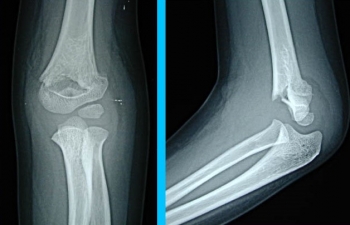

上腕骨顆上骨折の診断

X線写真が必要です

上腕骨内顆骨折、上腕骨外顆骨折など、類似した骨折もありますし、骨折の折れ方も程度がありますので、必ずX線写真を撮ってください